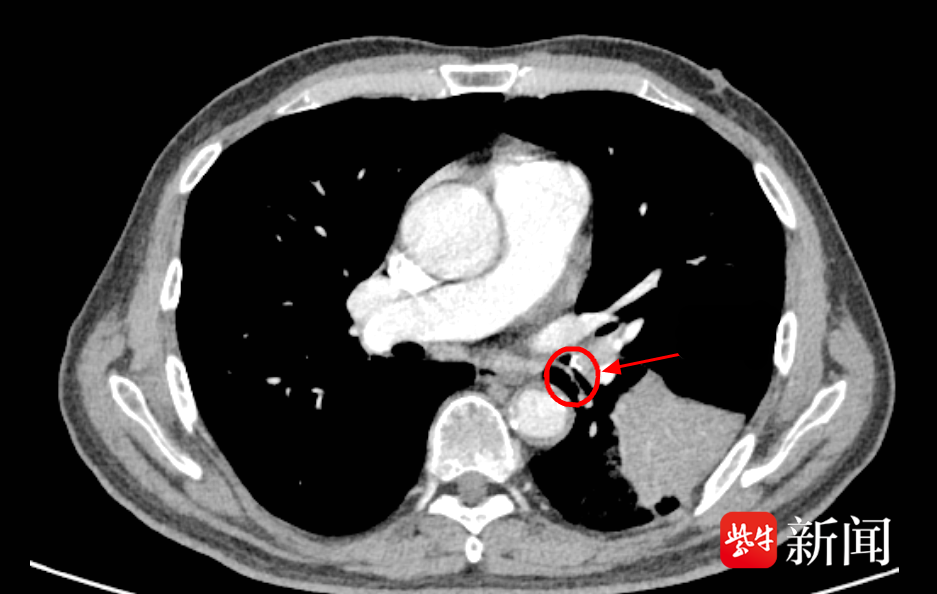

在充分的术前准备和风险评估后,由副主任医师高琳为李老伯实施支气管镜检查。当纤细的支气管镜缓缓进入李老伯的左肺下叶基底段时,一个令人意外的景象出现在屏幕上:在一片因炎症而充血水肿的支气管黏膜中,一个细长、坚硬的异物正死死地卡在管腔内,周围包裹着大量的脓性分泌物。

高琳小心翼翼地用异物钳将这个“潜伏”已久的元凶成功取出,竟然是一块长约1.6厘米的鱼骨!至此,真相大白。所谓的“肺部占位”,正是因为这块鱼骨堵塞气道,引发了堵塞性肺炎和肺不张,导致李老伯长达半个月的咳嗽和咳浓痰。